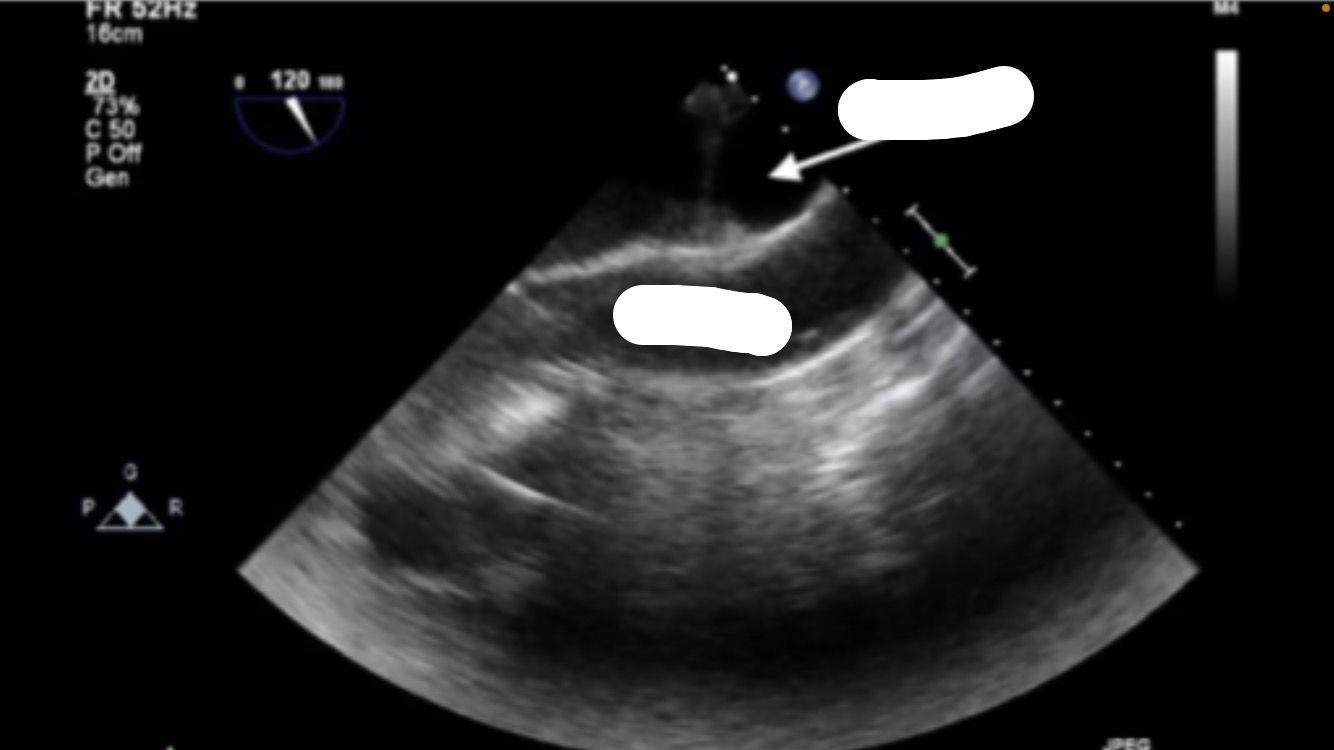

Mid-esophageal ascending aortic LAX

Mid-esophageal Long Axis view. LAX